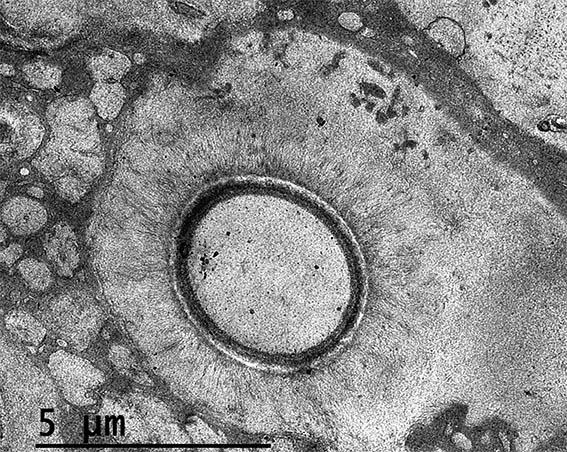

Figure 9. EM, original magnification, X2,500.